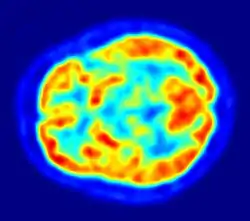

Brain Electrical Oscillation Signature Profiling (BEOSP or BEOS) is an EEG technique by which a suspect's participation in a crime is detected by eliciting electrophysiological impulses.[1][2]

It is a non-invasive, scientific technique with a degree of sensitivity and a neuro-psychological method of interrogation which is also referred to as 'brain fingerprinting'.